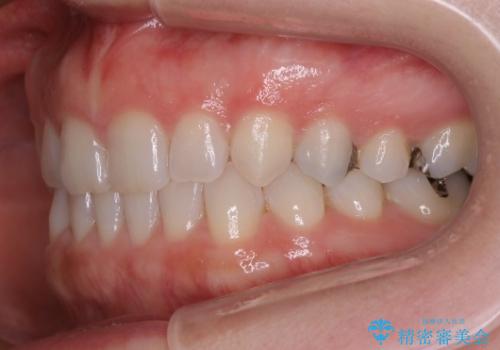

- 前歯の正中離開(すきっ歯)の改善を希望され来院された患者様です。

初診時の歯並びの状態としては、上顎中切歯間に1mm程の隙間があり、その他に見た目に関して気になるような問題点はない状態でした。

インビザライン(マウスピース)にて上顎のみの矯正治療を行いました。

見た目、嚙み合わせ及び、治療期間や施術内容に大変ご満足いただきました。